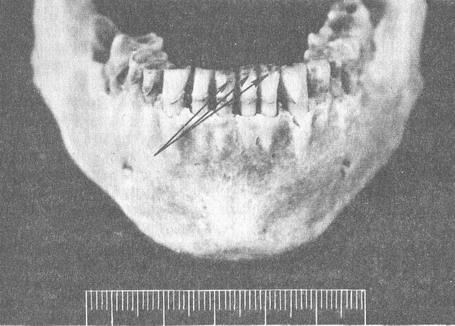

Симетричне бічне здавлення нижньої щелепи викликає перелом з локалізацією кісткового фрагмента з внутрішньої сторони. Пошкодження емалі у вигляді викришування по краю різців виникають при різкому змиканні щелеп внаслідок різноманітних механізмів, які однак вдається диференціювати (рис. 29).

При ударі по нижній щелепі спереду знизу, крім викришування емалі, можна діагностувати переломи тіла, гілок нижньої щелепи, крововиливи в м'які тканини в місці удару.